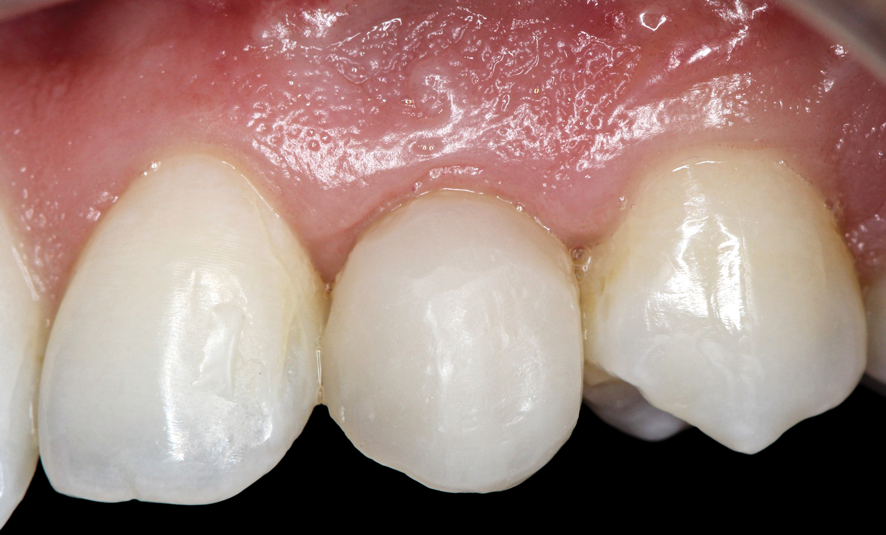

(56.) The provisional restoration was delivered and tightened to 15 Ncm while applying counter torque. Note that there is no pressure on the surrounding tissues and that the gingival embrasures were left open to allow for maximum incisal migration of the gingiva and papillae. The palatal and incisal surfaces were evaluated and modified to ensure that there was no contact throughout the excursive range.

Figure 56

(57.) The provisional restoration was delivered and tightened to 15 Ncm while applying counter torque. Note that there is no pressure on the surrounding tissues and that the gingival embrasures were left open to allow for maximum incisal migration of the gingiva and papillae. The palatal and incisal surfaces were evaluated and modified to ensure that there was no contact throughout the excursive range.

Figure 57